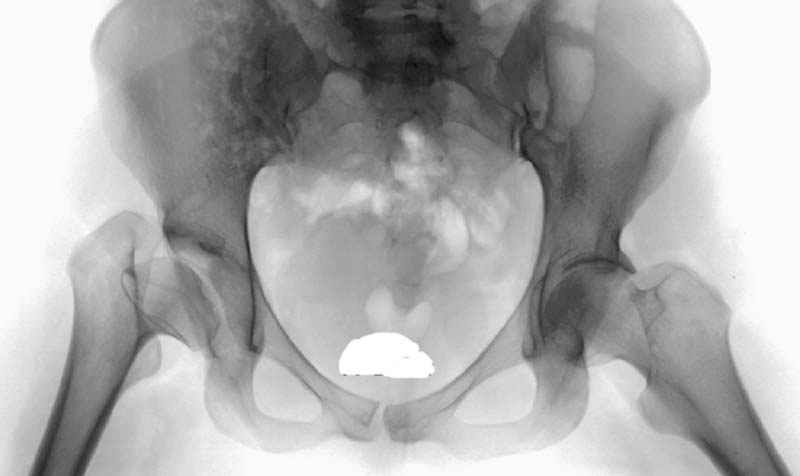

До операции #1

№ 1-3 до операции

1. Исходные рентгенограммы это рентгенограммы пациентов с дисплазией ТБС и варусной деформаций ШБК. Строго говоря, коксартроз, у них в зачаточном состоянии (суставная щель в верхнем отделе достаточной ширины, как правило, симметрична). Выполненные Вами столь успешные операции скорее профилактика коксартроза, а не его лечение <артроз - общее название болезней суставов, в основе которых лежит дегенерация суставного хряща, приводящая к его истончению и разволокнению, обнажению подлежащей кости, костным разрастаниям и нарушению конгруэнтности суставных поверхностей>. Но профилактика хорошая, здравомыслящая. В своих мыслях высказанных ранее касательно остеотомий при коксартрозе я имел в виду именно, подобный (см. определение) уже развившийся артроз. У Вас все-таки несколько иное: Пациенты еще по-ходят, однако, коксартроза им все равно не избежать, к сожалению, в том числе и к моему сожалению.